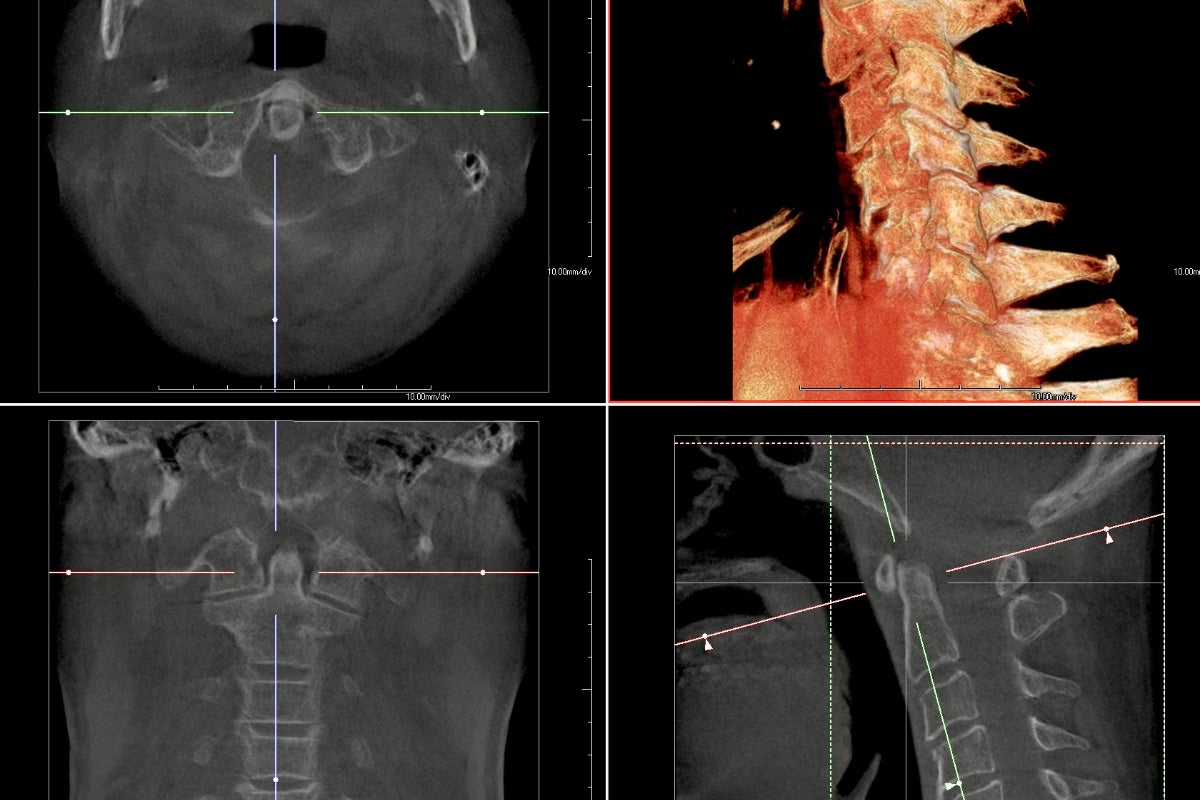

私が目指すのは、人の骨をパーツごとに細分化し、わずかな異変さえも見逃さない精度を誇る解析ソフトを作ることです。その設計技術や、試験などに必要な協力者(世界の医療者、研究者ら)はすでに揃っています。あとは、私自身が勇気を持って一歩踏み出し、やるだけだと思っています。